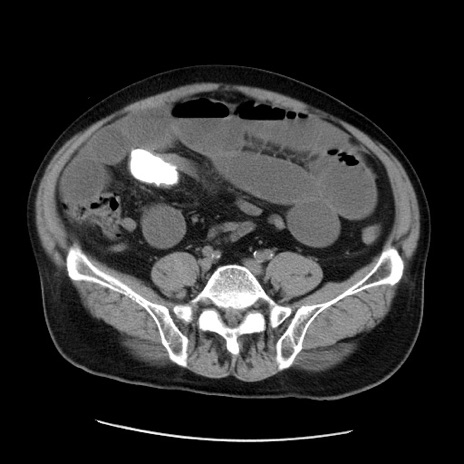

症例20(横断像)

【症例】 60歳代男性

【主訴】 腹部膨満、嘔吐

【現病歴】5日前頃より倦怠感を認め食事量減少し4日前の朝嘔吐、食事摂取困難となった。 3日前近医受診し点滴施行され整腸剤などを処方された。 当日他院を受診し、腹部膨満著明、炎症反応の上昇(CRP10.8、WBC11200)あり、紹介受診となる。

【身体所見】 意識JCS1 受け答えがはっきりしないBP 111/57mHg、 P 67bpm、、BT35.2°C、SpO2 97%(RA)、 腹部:膨隆、打診で鼓音あり、全体的に圧痛有り、腸蠕動音(-)、反跳痛ははっきりせず。

【データ】WBC 11400、CRP 14.20